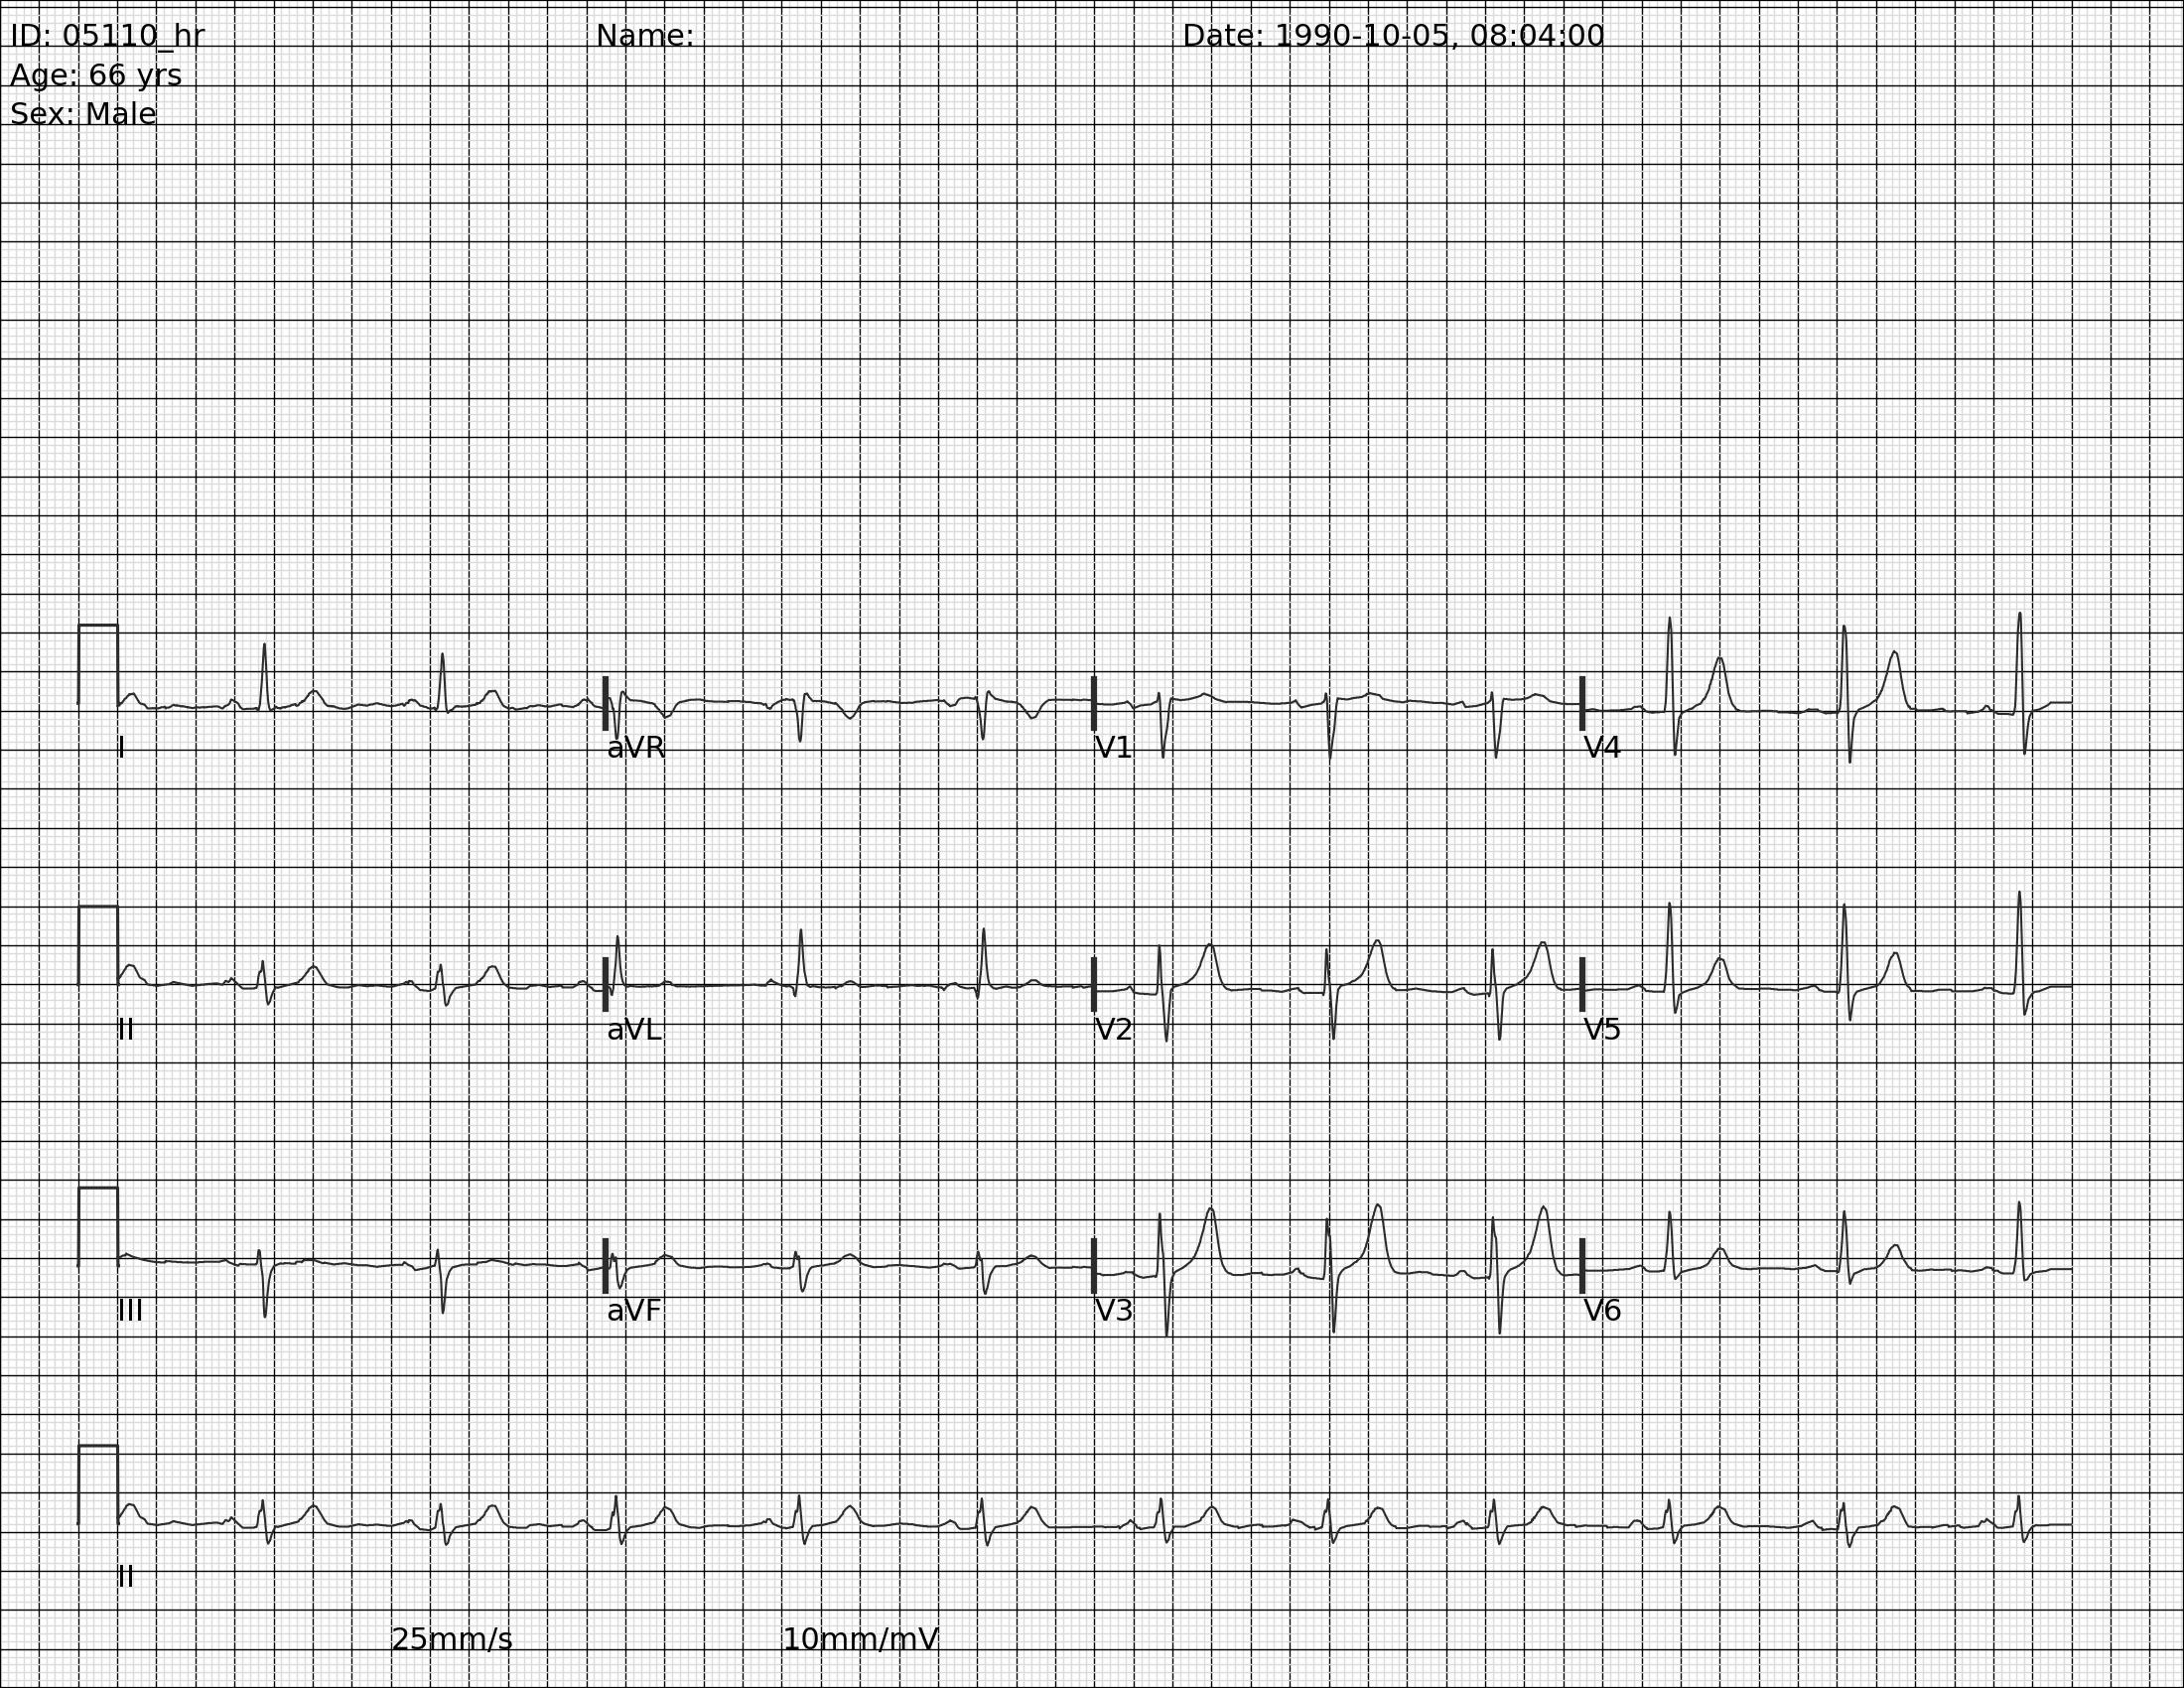

I occasionally peruse available Kaggle competitions to see if there’s something fun to explore. This week, I came across this competition around converting EKG images into time series data. This piqued my interest because context can give such a big advantage over a pure ML approach. I’m going to walk through some basics of EKGs and hopefully we can extract some time series data without using any ML. That said, there is obviously a place for computer vision to do a lot of the work that I’m going to write more deterministic code for.

For this, we’re going to go back to the red channel. We’ll use our previous analysis that we used to find rows that have no signal, and instead use it to find the rows that have our signals. There are 4 rows of signals. The first three have all 12 leads, and the bottom row is lead II going all the way across to be used for rate and rhythm.

Now we’ve found the parts of the image that have signal and we also identified the zero voltage line. Technically, zero voltage is defined as the voltage between the T wave and the following P wave, but this approximation of counting dark pixels in each row and identifying a local maximum seems to work incredibly well. You’ll notice that the bands are labeled 5-8 because I started at the top and each section of text or signal created a band. This will not always be consistent. In lead II, you can see that the label is a new band, but in the other rows, the label is included in the band. Depending on the patient, the device, and the strength of the lead connection, the amplitude of the signal can vary and overlap with the label (sometimes even overlap with the signal above or below).